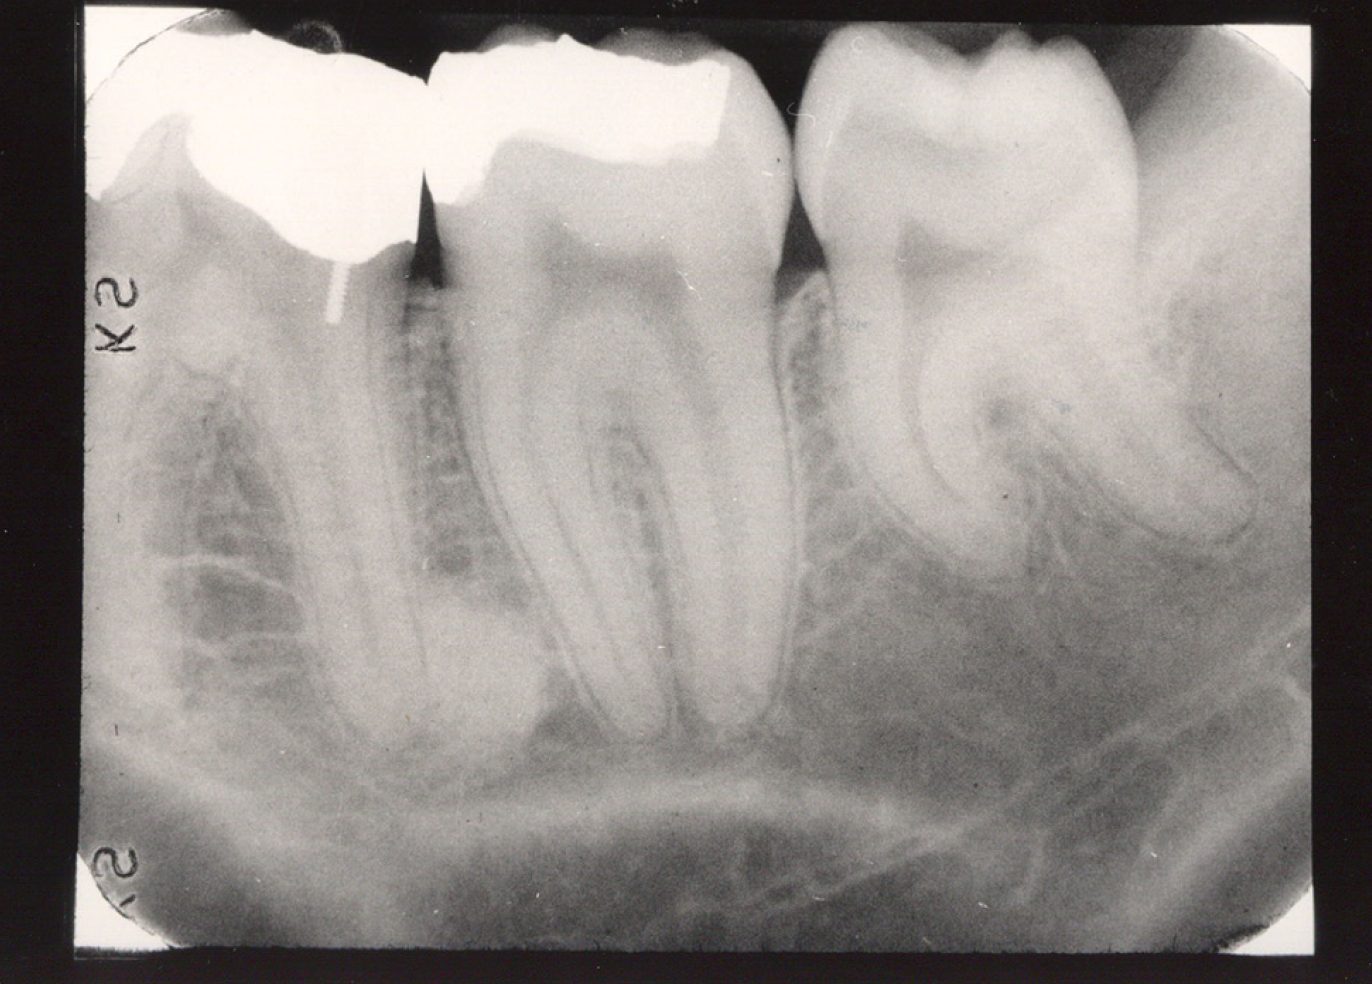

The occlusal image, as seen in Figure 3, is very useful in determining the buccolingual extension of pathologic conditions and provides additional information as to the extent and displacement of fractures of the mandible and maxilla. Occlusal radiographic images also aid in localizing unerupted teeth, retained roots, foreign bodies, and calculi in the submandibular and sublingual salivary glands and ducts. It should be noted that when imaging soft tissues, exposure time needs to be appropriately reduced.

Figure 3 - Occlusal Images

Figure 3